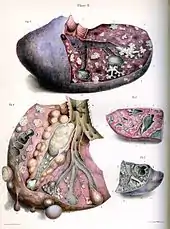

Tuberculosis is classified as one of the granulomatous inflammatory diseases. Macrophages, epithelioid cells, T lymphocytes, B lymphocytes, and fibroblasts aggregate to form granulomas, with lymphocytes surrounding the infected macrophages. When other macrophages attack the infected macrophage, they fuse together to form a giant multinucleated cell in the alveolar lumen. The granuloma may prevent dissemination of the mycobacteria and provide a local environment for interaction of cells of the immune system.[63] However, more recent evidence suggests that the bacteria use the granulomas to avoid destruction by the host's immune system. Macrophages and dendritic cells in the granulomas are unable to present antigen to lymphocytes; thus the immune response is suppressed.[64] Bacteria inside the granuloma can become dormant, resulting in latent infection. Another feature of the granulomas is the development of abnormal cell death (necrosis) in the center of tubercles. To the naked eye, this has the texture of soft, white cheese and is termed caseous necrosis.[63]

If TB bacteria gain entry to the blood stream from an area of damaged tissue, they can spread throughout the body and set up many foci of infection, all appearing as tiny, white tubercles in the tissues.[65] This severe form of TB disease, most common in young children and those with HIV, is called miliary tuberculosis.[66] People with this disseminated TB have a high fatality rate even with treatment (about 30%).[22][67]

In many people, the infection waxes and wanes. Tissue destruction and necrosis are often balanced by healing and fibrosis.[63] Affected tissue is replaced by scarring and cavities filled with caseous necrotic material. During active disease, some of these cavities are joined to the air passages (bronchi) and this material can be coughed up. It contains living bacteria and thus can spread the infection. Treatment with appropriate antibiotics kills bacteria and allows healing to take place. Upon cure, affected areas are eventually replaced by scar tissue.[63]